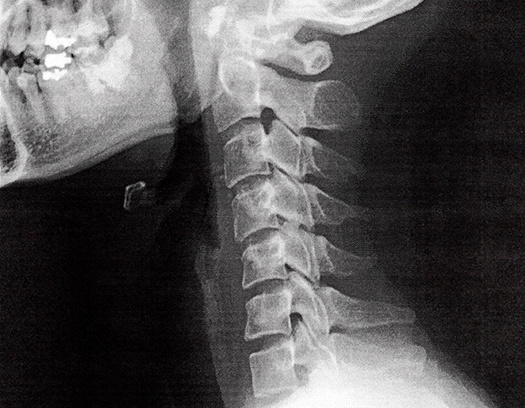

頚は、頚椎と呼ばれる7つの骨により構成されています。

椎間板の変性や靭帯が厚く硬くなることなどにより、頚部の痛みなどの症状が発現したものを総称して、頚椎症と呼んでいます。

整形外科などで、MRIやレントゲンを撮ると骨の位置異常が確認される場合があります。

骨の位置異常によって神経が圧迫されることもありますが多くの場合は筋肉が凝ることによって神経が圧迫されます。

MRIやレントゲンでは筋肉の硬さは映らず画像診断ではしびれの原因がわからないことがほとんどです。

また骨の位置異常が原因でしびれている場合でも根本原因は筋肉が緊張することにより骨の位置異常が起きるので、どちらにせよ筋肉をほぐし骨格を整える必要があります。